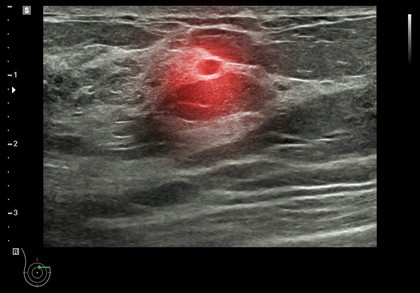

diagnostyka węzłów chłonnych

Diagnostyka węzłów chłonnych to niezwykle ważny element oceny stanu zdrowia pacjenta, który pozwala na wykrycie ewentualnych zmian chorobowych, takich jak infekcje, stany zapalne czy nowotwory. W Specjalistycznym Gabinecie Geriatryczno-Internistycznym Ewy Sawickiej w Częstochowie, pacjenci mogą liczyć na profesjonalne badania, które obejmują zarówno badanie palpacyjne, jak i zaawansowane metody obrazowania, takie jak ultrasonografia czy tomografia komputerowa. Dzięki temu lekarze są w stanie ocenić wielkość, kształt, konsystencję oraz ewentualne powiększenie węzłów chłonnych, co może świadczyć o obecności choroby.